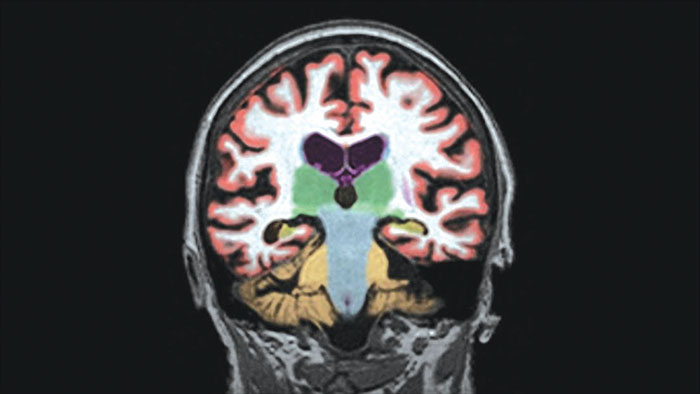

NeuroQuant®

MR NeuroQuant®*

Automated brain image analysis solutions

MR NeuroQuant®* automatically segments and measures volumes of brain structures and compares these volumes to standard norms.

Benefits

• Convenient and cost-effective means to gain reliable, objective measurements of neurodegeneration.

• Helps reduce the subjectivity of the diagnosis.

* NeuroQuant is a trademark of CorTechs Labs, Inc.